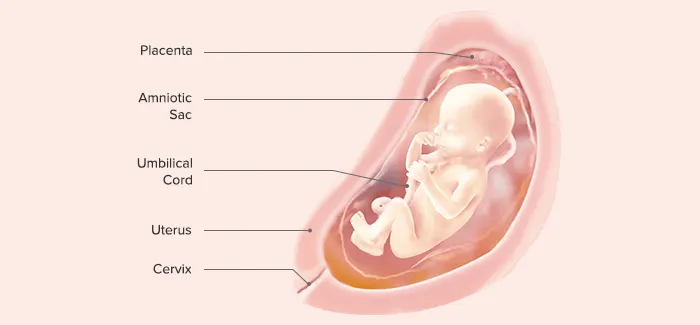

Brow know-how. Your baby can now furrow actual eyebrows! These fine hairs are pure white, as they don't contain any pigment yet. Eyelids have developed too, although they'll stay fused shut until about 28 weeks.

Inside workout. Now that baby’s arms and legs are proportional (but not their final size), he or she is busy kicking, grasping, flexing and clasping those little hands. Tiny fingernails now completely cover the fingertips–and they keep growing. In fact, you may need to trim your baby's nails straight after birth to avoid scratching that baby-soft skin.

Prepare for padding. At this point, your baby only has one per cent body fat, but will keep adding on layers of brown fat to help produce and retain body heat.

Did you know? Your baby could be frowning with his or her newly developed facial muscles and eyebrows. His or her eyebrows and hair look white, as they don’t contain any pigment yet. Baby can also make a fist and may even grab onto the umbilical cord, but not strongly enough to do any harm.